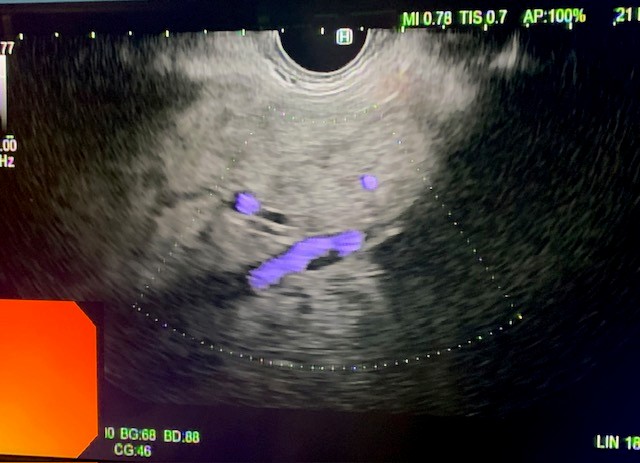

Under general anesthesia, esophagogastroduodenoscopy (EGD) was done using a gastroscope (Olympus America) and there were no esophageal or gastric varices noted. Next, EUS linear array echoendoscope (Olympus America) was passed into the esophagus and advanced into the stomach. The ultrasound image of the liver showed diffuse fatty infiltration. We performed portal pressure gradient using a 25-gauge Cook Echo Tip Insight needle (Cook Endoscopy, Winston Salem, NC). Pulse wave Doppler was used to confirm the middle hepatic vein. From the stomach through the left lobe of the liver, the middle hepatic vein was accessed, and three pressure measurements were taken using digital manometry (Figure 2). The average of 3 measurements from the middle hepatic vein was 17 mmHg. Pulse wave Doppler was used to confirm the left portal vein (Figure 3). Then from the stomach we measured the portal vein pressure by accessing the left portal vein and the average of three measurements was 18 mmHg (Figure 4), giving her a PPG of 1 mmHg. Using Doppler, we ensured there was no bleeding when the needle was withdrawn from both veins (Figure 5 and 6). After the portal pressure gradient measurement, liver core biopsies were done using a 19-gauge Boston Scientific FNB needle (Boston Scientific Marlborough, MA). From the stomach, the left liver lobe was biopsied with the use of EUS to confirm the absence of blood vessels in the needle’s trajectory. One pass and three actuations using the wet heparin technique was performed. The right liver lobe was biopsied from the duodenum and similar methodology was done using the same needle and technique. No bleeding was noted. Both core liver biopsies were sent in formalin to the pathology department for further evaluation.

Figure 3: Pulse wave Doppler of left portal vein prior to manometry.